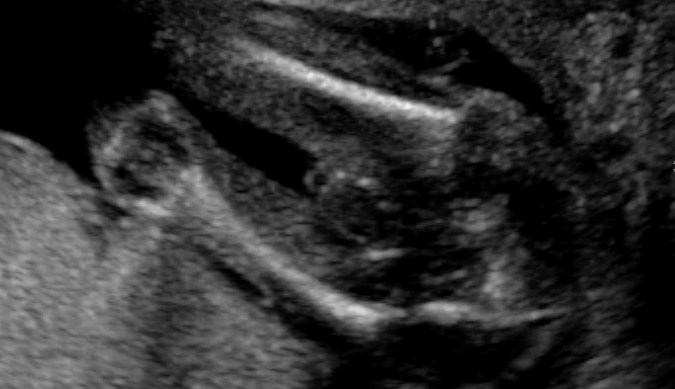

Tech said boy! Think so?

Can you ladies help please? This is my 20 weeks scan. Tech said it's 90% boy as she can see penis. Do you ladies think so? She did not point out the parts to me. And when I look at these pics, I think it's the boy bits I am looking at, but I am not too sure???